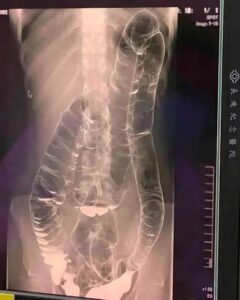

O pacientă tânără, cu istoric de constipație neglijată ani la rând, a ajuns la urgență medicală după mai bine de două săptămâni fără tranzit intestinal. Investigațiile efectuate au inclus o radiografie care a dezvăluit un colon mult peste dimensiunile obișnuite, dilatat până aproape de nivelul inimii. Imaginea surprinsă i-a alarmat pe medici: tubul colonic părea neted, fără pliurile caracteristice (haustre), semn al unei presiuni interne extreme și al unei suferințe de durată.

Colon dilatat: ce au văzut medicii și de ce e periculos

Când reziduurile stagnează prea mult, colonul se adaptează forțat prin dilatare. La această pacientă, întinderea peretelui intestinal a fost atât de pronunțată încât aspectul ondulat normal a dispărut, iar structura a devenit rigidizată. În astfel de situații, motilitatea este grav compromisă, ceea ce perpetuează cercul vicios al constipației. Pot apărea complicații serioase: obstrucție intestinală (blocaj complet), presiune pe organele vecine, inflamație și infecții locale prin stagnare prelungită a conținutului, până la necroză tisulară în zonele suprasolicitate.

Din perspectivă clinică, un colon atât de distensat poate mima alte patologii intraabdominale și poate ascunde semnele de alarmă. Radiologia devine esențială pentru a aprecia gradul de dilatare și riscul de perforație, iar deciziile terapeutice se iau rapid pentru a evita evoluția către complicații acute.

În cazul discutat, imaginile au documentat o dilatare marcată, cu pierderea pliurilor colonice tipice și ascensionarea buclelor până aproape de compartimentul toracic. Acest aspect imagistic, corelat cu absența tranzitului de peste două săptămâni, conturează severitatea stazei fecale și justifică intervenția medicală de urgență pentru restabilirea funcției digestive.